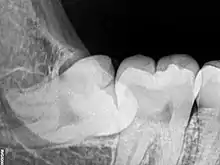

Risk factors of inferior alveolar nerve damage

Temporary and permanent inferior alveolar nerve (IAN) damage is a known complication of the surgical removal of impacted lower third molars, happening in 1 in 85 patients and 1 in 300 extractions, respectively. Studies have shown that certain risk factors may increase the likelihood of IAN damage. Proximity of the impacted third molar root to the mandibular canal, which can be seen in radiographs, has been shown to be a high-risk factor for IAN damage. Alongside this, the depth of impaction of the tooth, surgical technique and surgeons experience are all contributing risk factors for IAN damage during this procedure. Careful case-by-case consideration is crucial to avoid this risk.[39]